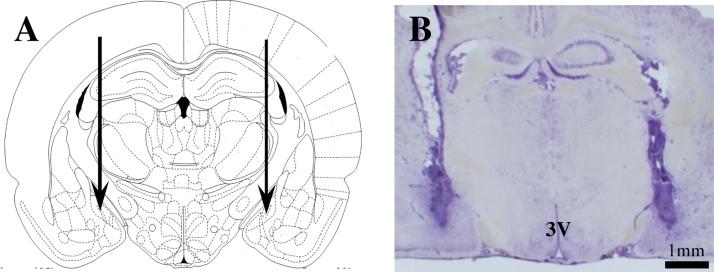

The medial amygdala (MeA) is crucial for sexual behavior; kisspeptin (Kiss1) also plays a role in sexual function. Kisspeptin receptor (Kiss1r) knockout mice display no sexual behavior. Recently Kiss1 and Kiss1r have been discovered in the posterodorsal subnucleus of the medial amygdala (MePD). We hypothesised that Kiss1 in the MePD may have an influence on male sexual behavior. To test this we bilaterally cannulated the MePD and infused kisspeptin-10 in male rats. This caused the rats to have multiple erections, an effect specific to Kiss1 receptor activation, because Kiss1r antagonism blocked the erectile response. When Kiss1 was infused into the lateral cerebroventricle, there were no observed erections. We also measured the plasma levels of LH when Kiss1 is infused into the MePD or lateral cerebroventricle; Kiss1 increased plasma LH to comparable levels when infused into both sites. We conclude that Kiss1 has a role in male sexual behavior, which is specific to the MePD.

内侧杏仁核(MeA)对性行为至关重要;亲吻素(Kiss1)在性功能中也发挥作用。亲吻素受体(Kiss1r)基因敲除小鼠没有性行为。最近,在内侧杏仁核后背部亚核(MePD)中发现了Kiss1和Kiss1r。我们假设MePD中的Kiss1可能对雄性性行为有影响。为了验证这一点,我们对雄性大鼠双侧植入MePD插管,并向其中注入亲吻素-10。这导致大鼠多次勃起,这是Kiss1受体激活特有的效应,因为Kiss1r拮抗剂可阻断勃起反应。当将Kiss1注入侧脑室时,未观察到勃起现象。我们还测量了向MePD或侧脑室注入Kiss1时血浆促黄体生成素(LH)的水平;当向两个部位注入Kiss1时,血浆LH升高至相当水平。我们得出结论,Kiss1在雄性性行为中起作用,且这种作用对MePD具有特异性。